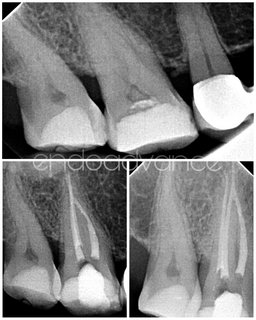

Αρχική ενδοδοντική θεραπεία σε άνω γομφίο με περίπλοκη ανατομία